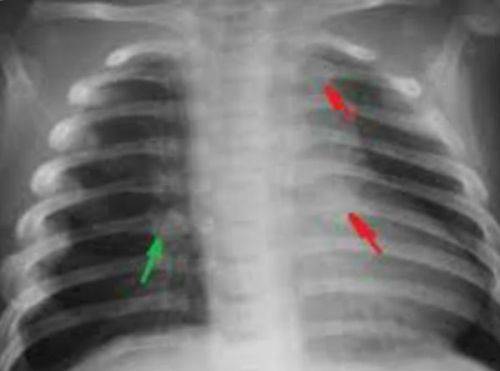

Плеврит — скопление воспаленной жидкости в правой плевральной полости, является осложнением пневмонии, признаком туберкулеза легких. Раздражение плевральных листков вызывает сильную боль сзади в области нижних ребер и в подреберье с иррадиацией в живот, невозможность глубокого дыхания, одышку, отставание правой стороны грудной клетки в акте дыхания.

На рентгеновском снимке видна жидкость в плевральной полости справа, чтобы точно узнать причину плеврита необходимо сделать повторный снимок после ее удаления

У пациентов общее тяжелое состояние, выраженная интоксикация, ознобы, высокие скачки температуры. Плеврит может быть вызван абсцессом легкого, раковой опухолью, нагноившимися бронхоэктазами.